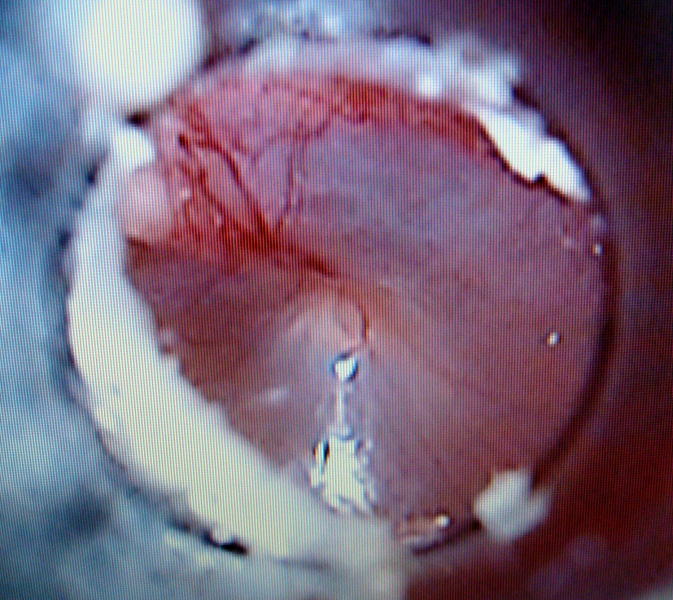

外耳炎のお話(2)

外耳炎は、耳穴から鼓膜の手前までの炎症です。耳垢や痒みを伴うことが多く、

治療せずに放っておくと、さらに鼓膜の奥にまで炎症が進むこともあります。

鼓膜より奥に炎症が起こったものはより重症で治りにくく、中耳炎とよばれて

います。以下のような症状がある場合は、早めに受診してください。

●耳を掻く ●頭や耳を振る ●耳の内側が赤く腫れている ●耳垢が多く、

臭いニオイがするなど

当院では、飼い主様も一緒に耳の中を観察できるデジタル耳鏡を導入しています。

デジタル検耳鏡と外耳道、鼓膜の写真